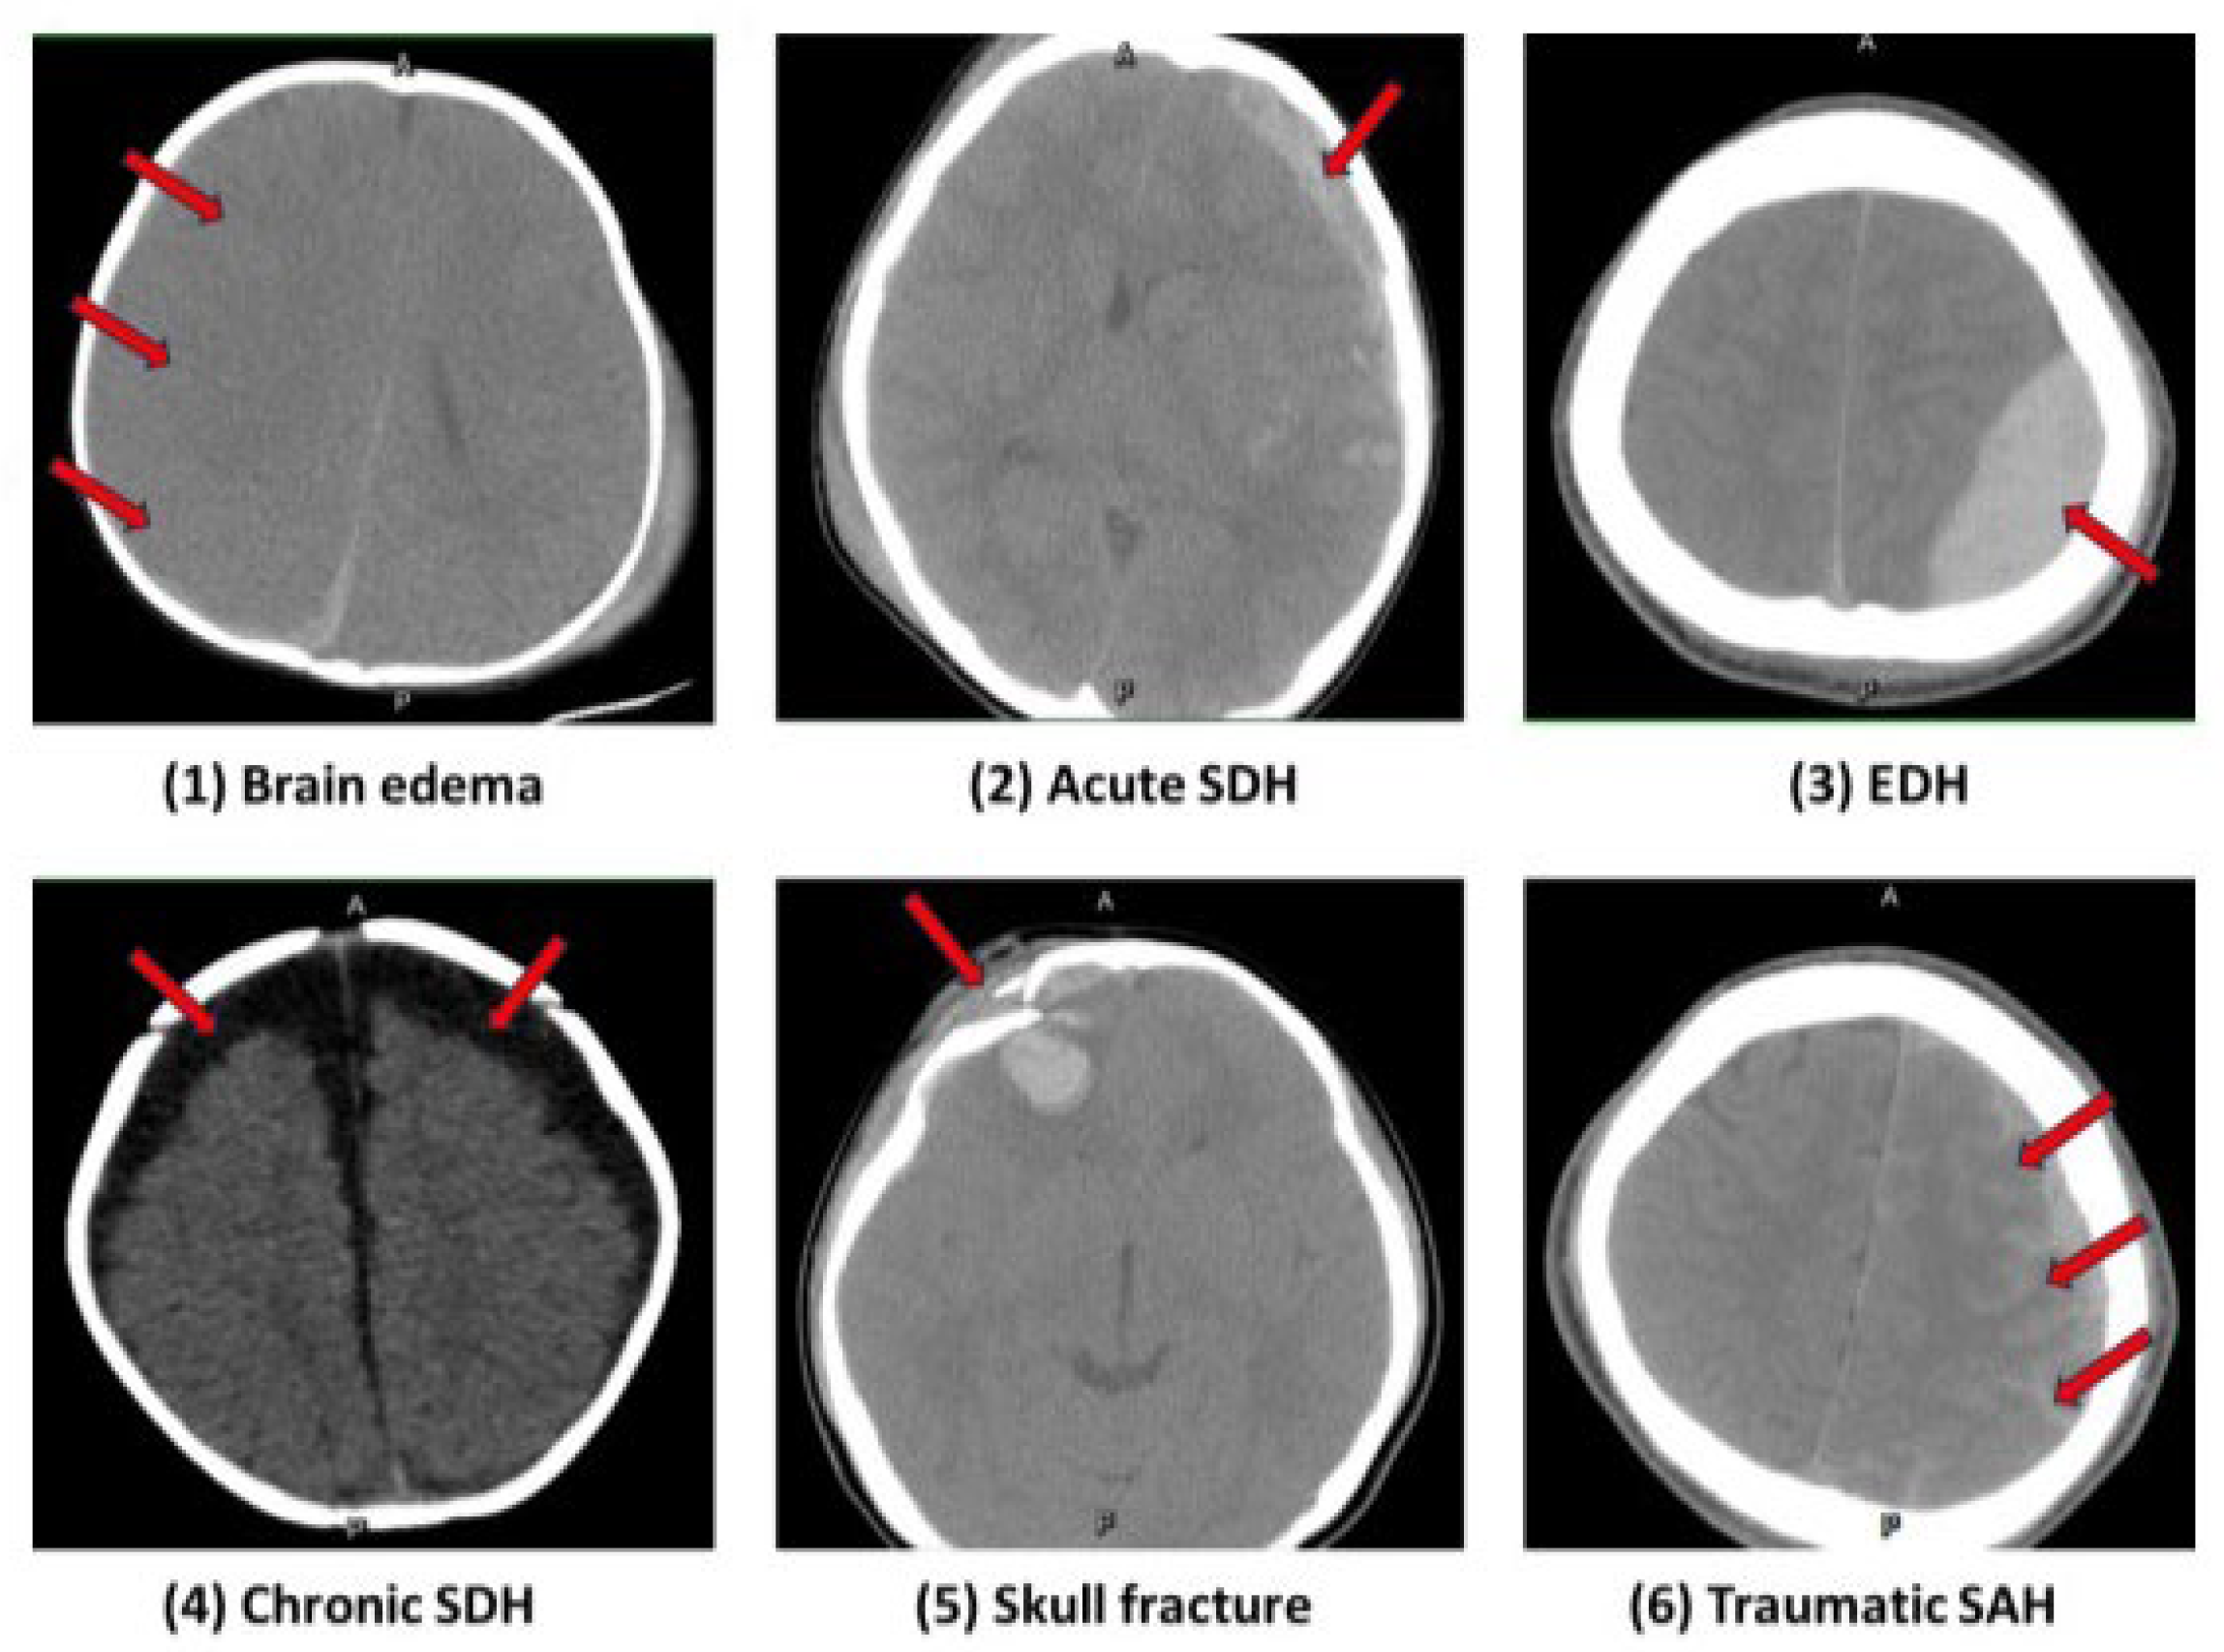

3.1. Imaging Findings

| Brain edema | 45 | 30.0 |

| Acute subdural hematoma | 41 | 27.3 |

| Epidural hematoma | 32 | 21.3 |

| Chronic subdural hemorrhage | 15 | 10.0 |

| Skull fracture | 10 | 6.7 |

| Traumatic subarachnoid hemorrhage | 7 | 4.7 |